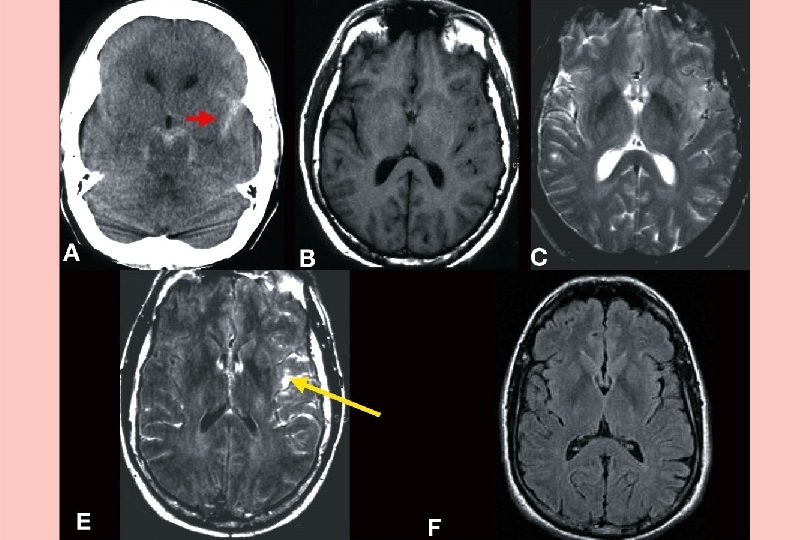

Sub Arachnoid - thunderclap headache

Thunderclap headache - RVS n lasts 1 -3 mths. n Primary or secondary n Normal CT, LP. Needs CT angio. n Can get complications